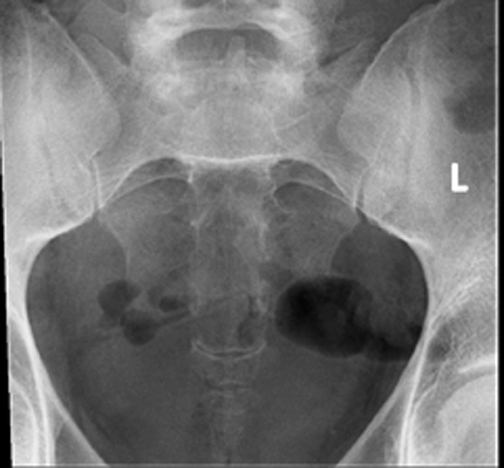

Coccyx X Ray Positioning. Palpate bottom of coccyx to center 4. Ensure no rotation of the pelvis. • patient position—supine position • part position • align midsagittal plane to cr and midline of table and/or ir. The patient lies on his back, bends his legs at the knee and hip joints (or only at the knees).

The arms are extended along the body. #sacrum#coccyxhello!!!!what’s up guys, kaise ho dosto? Cr angled caudad 10 °. Ensure no rotation of body and pelvis for true lateral position. 10 degree caudal tube angle. Sacrum • pathology of the sacrum, including fracture.

In coccygodynia, pain is most severe in the sitting position. Cr angled caudad 10 °. Aur samaj lenge ki sacr. The arms are extended along the body. 3 views • ap sacrum with central ray angled 15 degrees cephalad • ap coccyx with central ray angled 10 degrees caudad • lateral sacrum/coccyx.

3 views • ap sacrum with central ray angled 15 degrees cephalad • ap coccyx with central ray angled 10 degrees caudad • lateral sacrum/coccyx. In coccygodynia, pain is most severe in the sitting position. Legs extended with a support under the knees. The patient can be either on the left or right lateral recumbent position, depending on which is more comfortable; This can dramatically decrease the amount of radiation delivered to the patient and can especially decrease the amount of radiation delivered to.

Sacrum • pathology of the sacrum, including fracture. Palpate bottom of coccyx to center 4. It is used in conjunction with the ap projection. This projection helps to visualize pathology of the coccyx, especially fractures.to minimize superimposition of structures over the coccyx region, the urinary bladder and large colon should ideally be emptied before this examination 1. Coccygeal segments should appear open on radiograph, if not they may be fused, or an increase on central ray angulation.